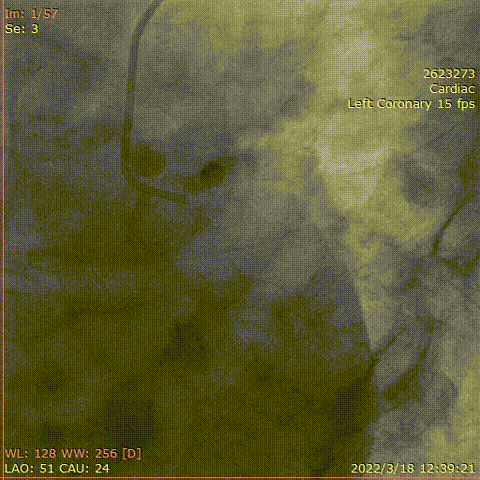

对右冠脉行介入治疗,钙化较重

对右冠脉行介入治疗,右冠脉中段预扩张后超声导管仍通过困难

选择1.5mm磨头高速旋磨